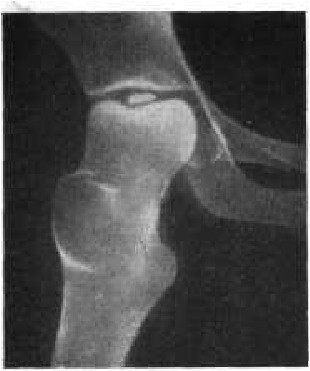

Верхний конец длинной бедренной кости имеет сложное строение. Закругление на конце – головка кости, более узкая часть, соединяющая головку с телом кости – это шейка, а с двух сторон этой шейки есть костные выступы – вертелы (особенно заметен наружный), к ним прикрепляются мышцы. Шейка – самая хрупкая часть бедренной кости.

Шейка бедра — это место на бедренной кости, где нога соединяется с тазом. Она находится чуть ниже шарообразной головки бедренной кости, которая крутится в гнезде тазобедренного сустава. На этом рисунке перелом шейки бедра — слева.